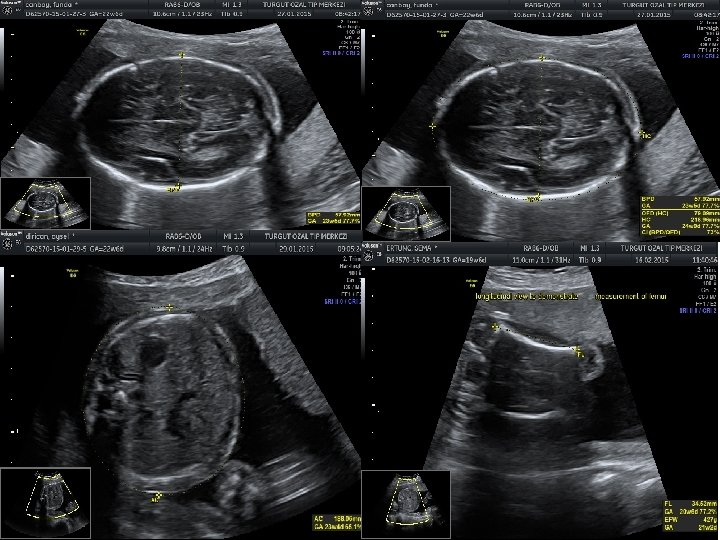

• Anormal biyometri saptanan hastalarda anormal fetal büyümenin fetal, plasental veya maternal nedenlerinin belirlenmesi amacıyla klinik ve ultrasonografik muayene yapılması gerekir. • Tahmini fetal ağırlığın saptanması için birçok formül önerilmiştir. • Bu formüllerin birçok parametre içermesine (biparietal çap, oksipitofrontal çap, baş çevresi, femur uzunluğu, abdominal çap ve abdominal çevre) karşın tahmini fetal ağırlıkta yanılma ortalama %10 -15 arasındadır ve bu oran %25’e kadar çıkabilmektedir.

• Gebelik yaşının tespitinde erken gebelikte en değerli ultrasonografik ölçüm parametresi CRL’dir. • İkinci trimesterda ise BPD ve HC daha doğru sonuçlar verir. • Üçüncü trimesterda ise en değerli ölçüm AC’dir. AC fetal büyüme ve ağırlık için en değerli parametredir.